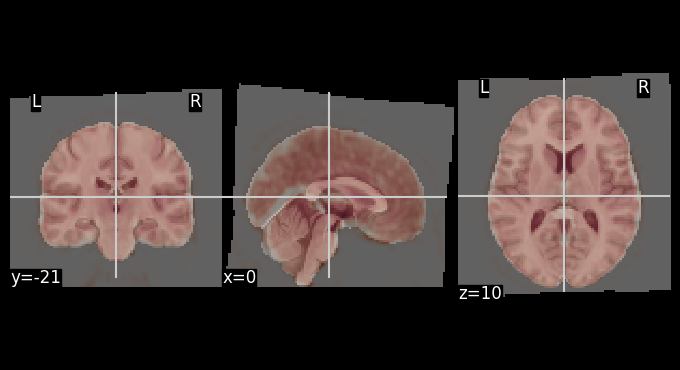

The mean BOLD image after motion correction was registered to the MNI template. The overlays below allows for visual inspection of alignment quality.

# Get mean BOLD image

mean_bold = image.mean_img(result_parallel.bold_preproc[0], copy_header=True)

# Overlay of the mean bold image on MNI background template

plotting.plot_stat_map(stat_map_img=mean_bold,

bg_img=template,

transparency=0.4,

colorbar=False)

<nilearn.plotting.displays._slicers.OrthoSlicer at 0x7ff620ef4cd0>